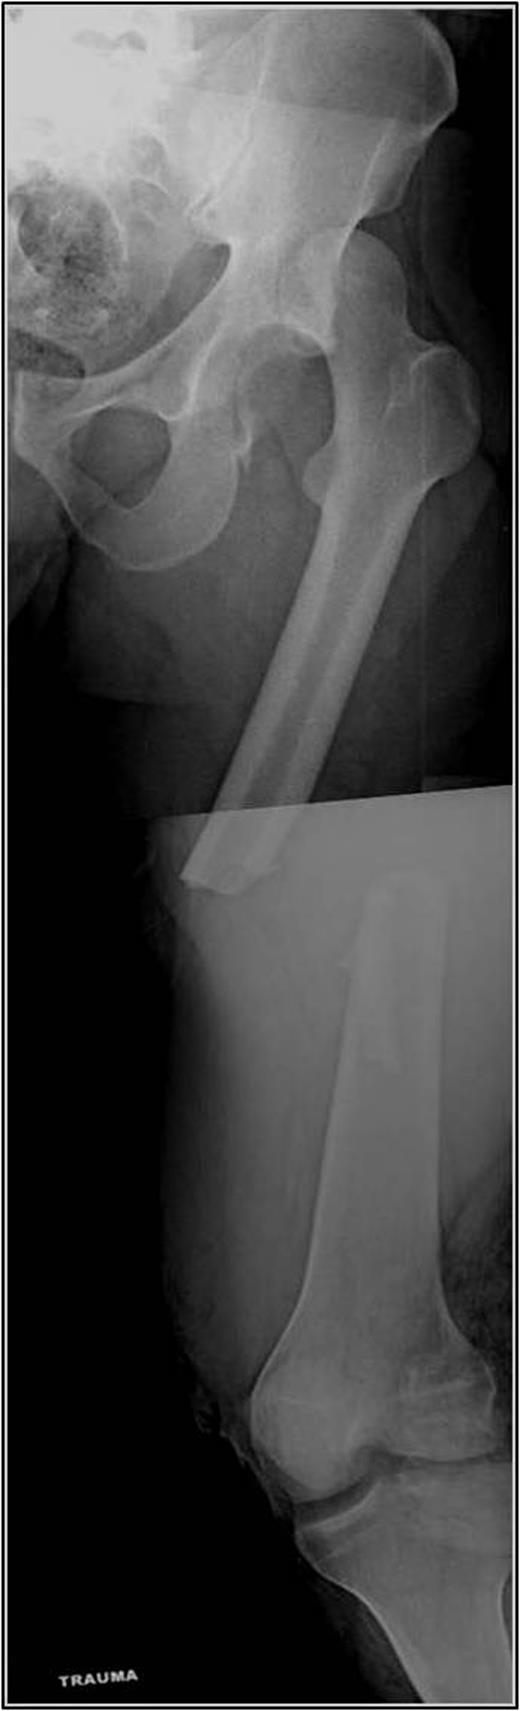

A 35-year-old male was involved in a high-speed urban dirt biking accident. The patient was stable with a GCS of 15 and was neurovascularly intact. His left knee exhibited a 10 × 20 cm medial traumatic arthrotomy and his thigh compartments were soft and compressible. Imaging revealed a left hip postero-superior dislocation, posterior wall acetabular fracture, ipsilateral transverse femoral diaphyseal fracture and an engaging hill-sachs-type lesion of the femoral head with the postero-superior acetabulum (Figs 1–3). Cefazolin, gentamicin and tetanus prophylaxis were administered along with a bedside washout of the traumatic arthrotomy. The patient was medically cleared for operative intervention as all blood work and further imaging were normal.

AP left hip demonstrating a diaphyseal transverse femur fracture with ipsilateral hip dislocation.

AP left femur of type B floating hip with associated hip dislocation. The medial knee soft tissue injury is also appreciated.